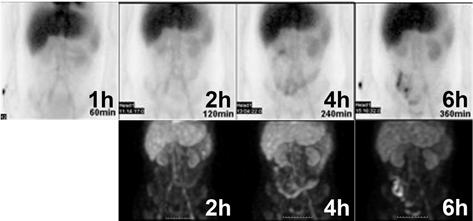

A 34-year-old female complained of diarrhea possibly due to PLE, as her mean right atrial pressure was 19 mmHg. She was born with tricuspid atresia and pulmonary atresia, and underwent the APC Fontan operation when she was 9 years old. She had suffered from severe hypo-albuminemia since she was 20 years old, and had a serum albumin level of approximately 1.2–1.4 mg/dL. Albumin scintigraphy revealed intestinal albumin loss including descending portion of duodenum (Fig. 1). Gastroduodenal endoscopy was performed to elucidate the causes of the albumin loss, during which edematous intestinal mucosa and duodenal villi were observed. Many villi were white, which was presumably related to enlargement of the lymphatic vessels (Fig. 2 A–C).

Fig. 2 Endoscopic images of the duodenum

(A) Macro-image of the intestinal mucosa. Intestinal mucosa and duodenal villi were edematous. White spots on the surface were lymphedema (inside the circles). (B) and (C) Magnified images of duodenal villi. White spots on the villi (arrowheads) indicate enlarged lymphatic vessels.